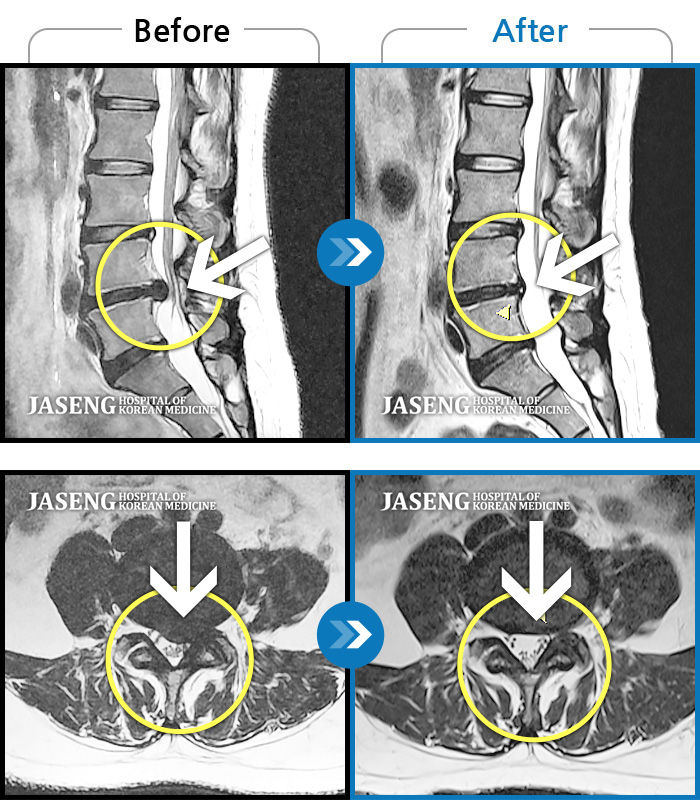

허리디스크

광주 · 김동은 원장

좌측 골반 및 종아리부터 발까지 이어지는 저림과 통증으로 내원하셨습니다.

촬영시기

2023.10.03 ~ 2025.08.14

2025.08.22